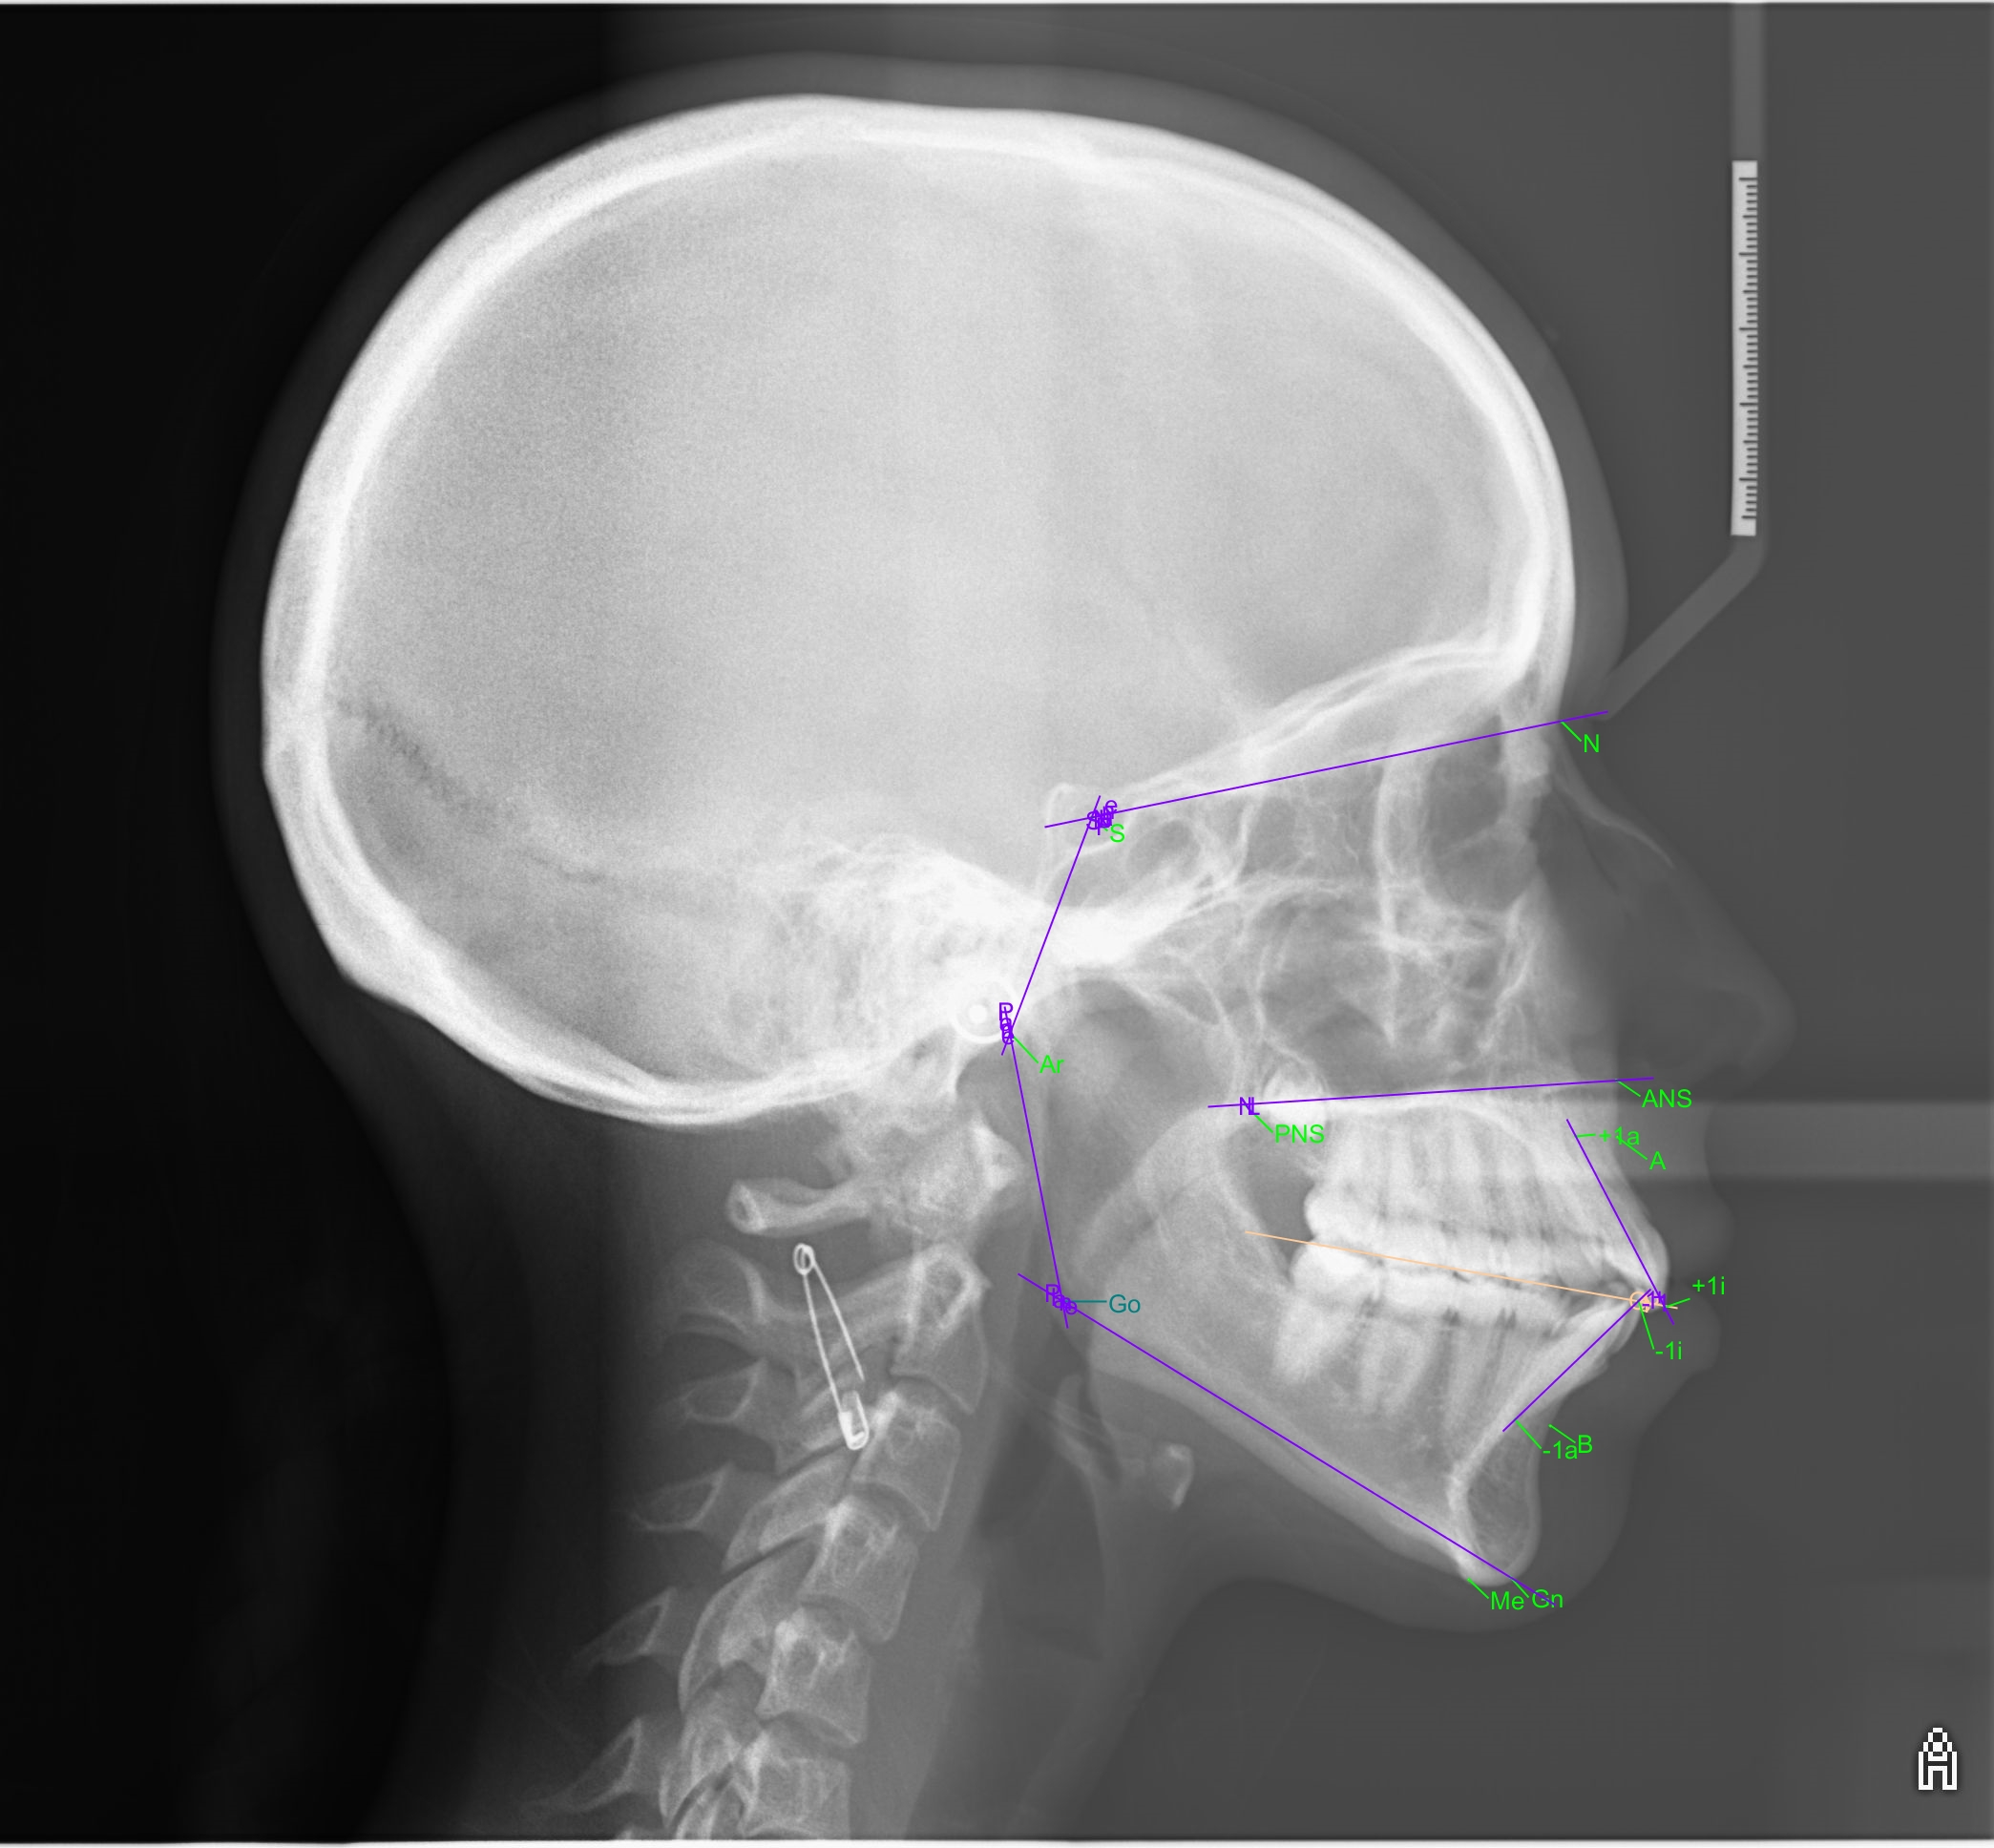

Al termine del trattamento, vale a dire solo 8 mesi dopo, l‘analisi cefalometrica di controllo ha indicato un miglioramento degli assi incisivi nonostante la correzione di una DDM moderata.

Gli allineatori SPARK hanno pertanto consentito al Dr. Pierre-Antoine Dian di ottenere una buona espansione delle arcate, un perfetto controllo del torque e una risoluzione dell‘affollamento anteriore grazie ai protocolli utilizzati e alla predicibilità dei movimenti oltre alla flessibilità fornita dal software Approver.